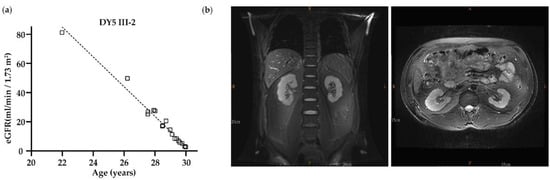

| DY5 | c.179G > A | p.Gly60Asp | VUS 2 | LP | Delayed maturation and decreased extracellular excretion | |||